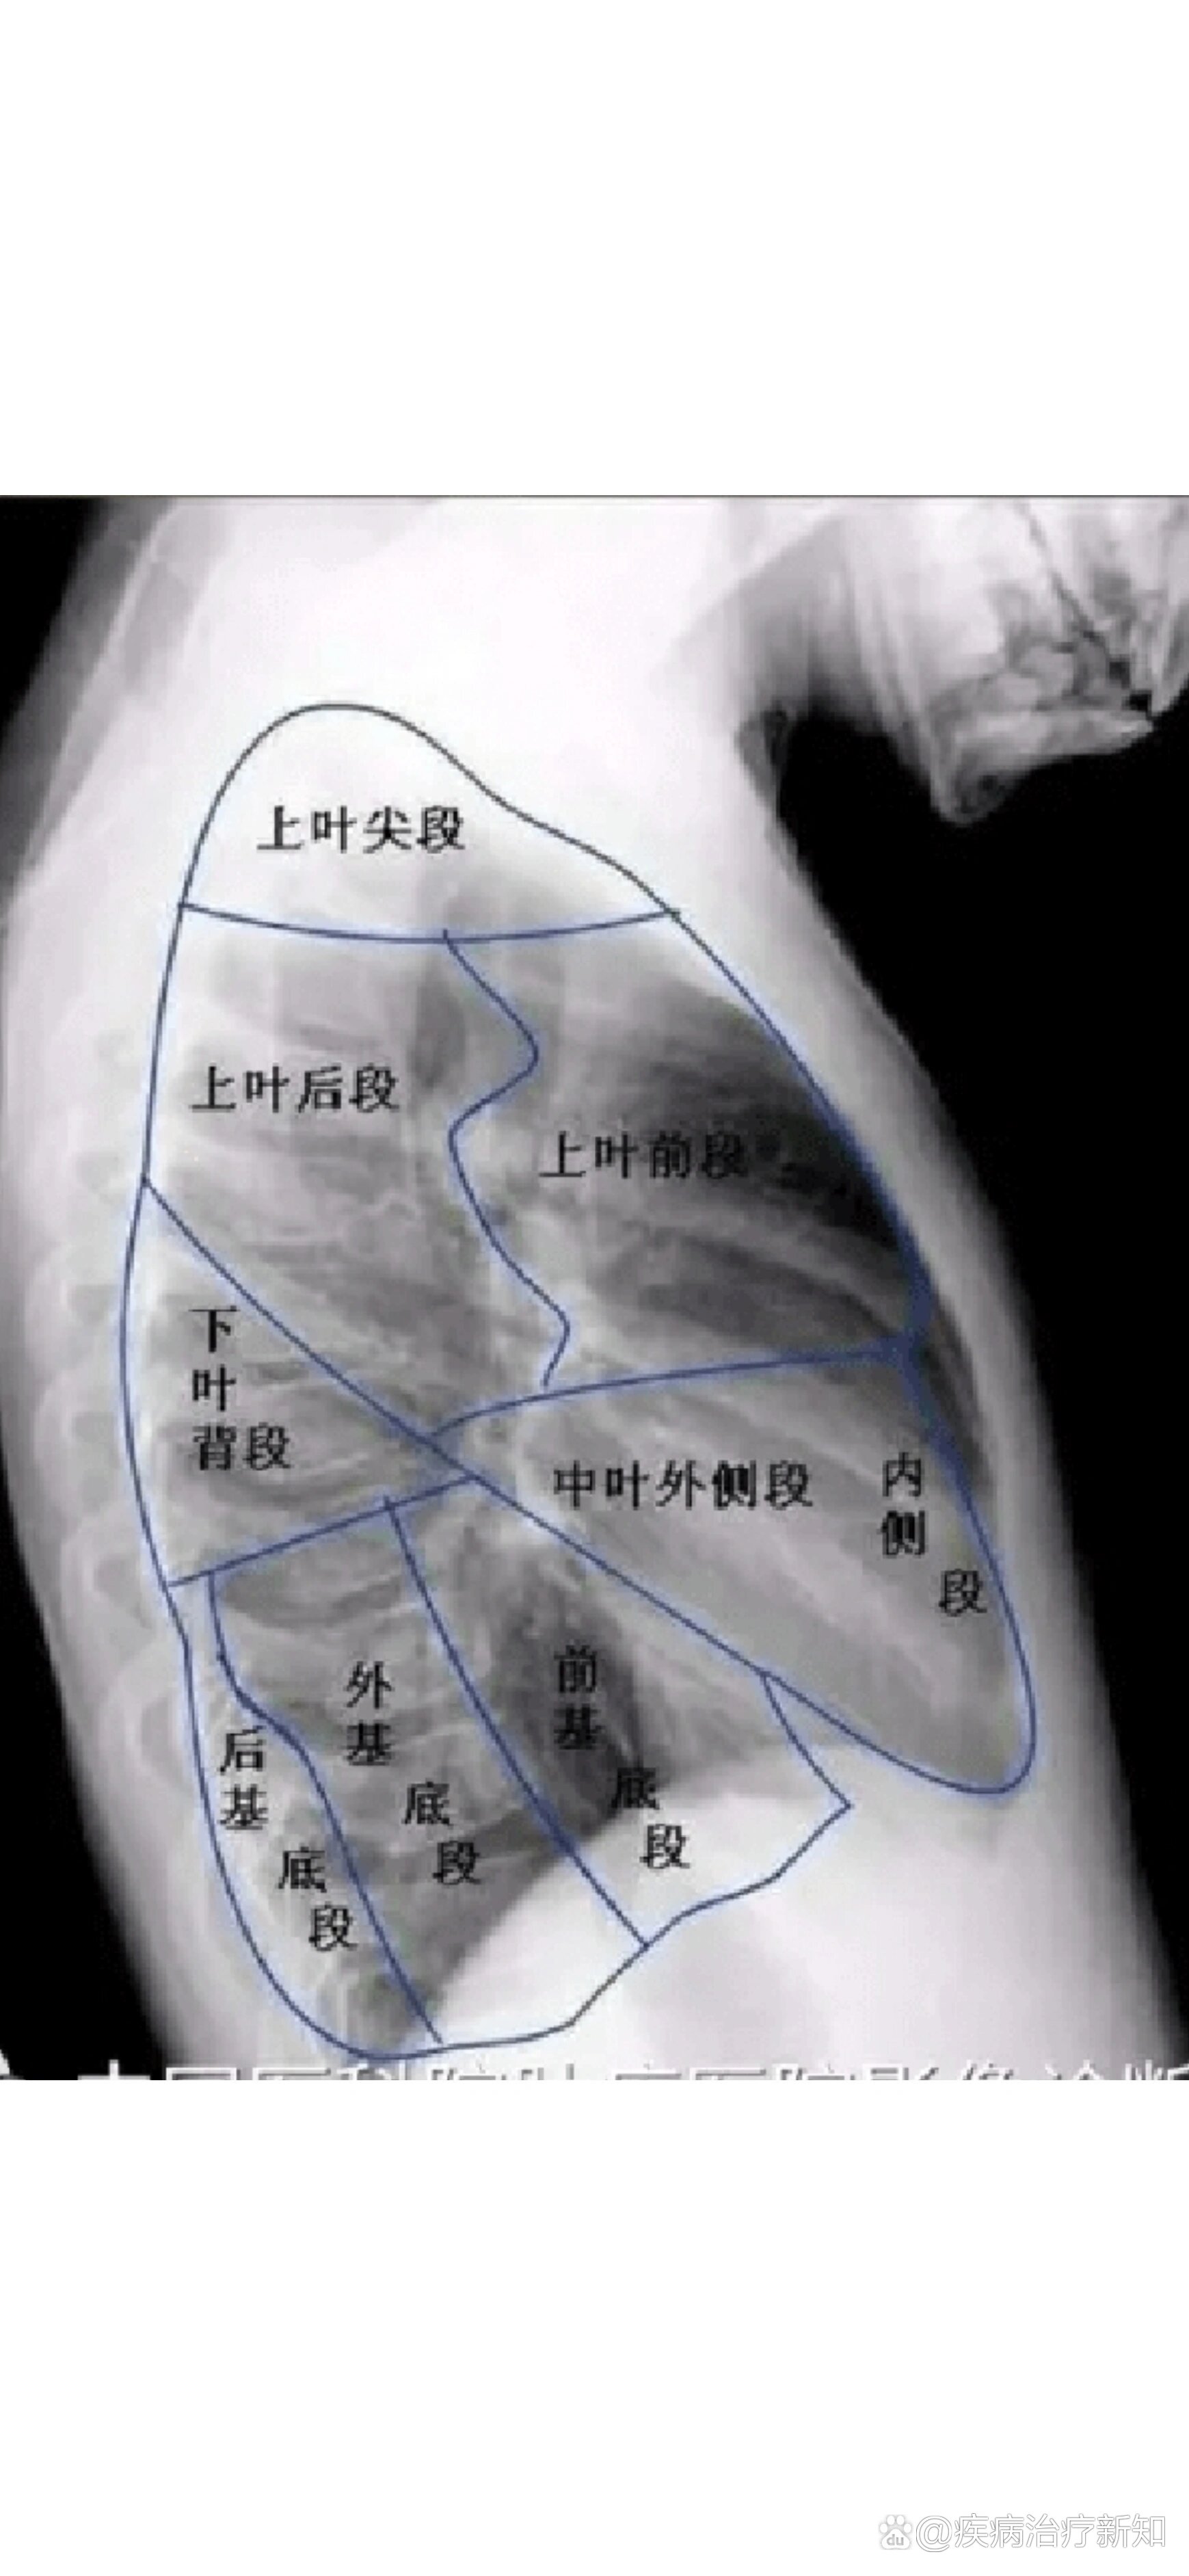

学习胸片(一,肺解剖 描述)